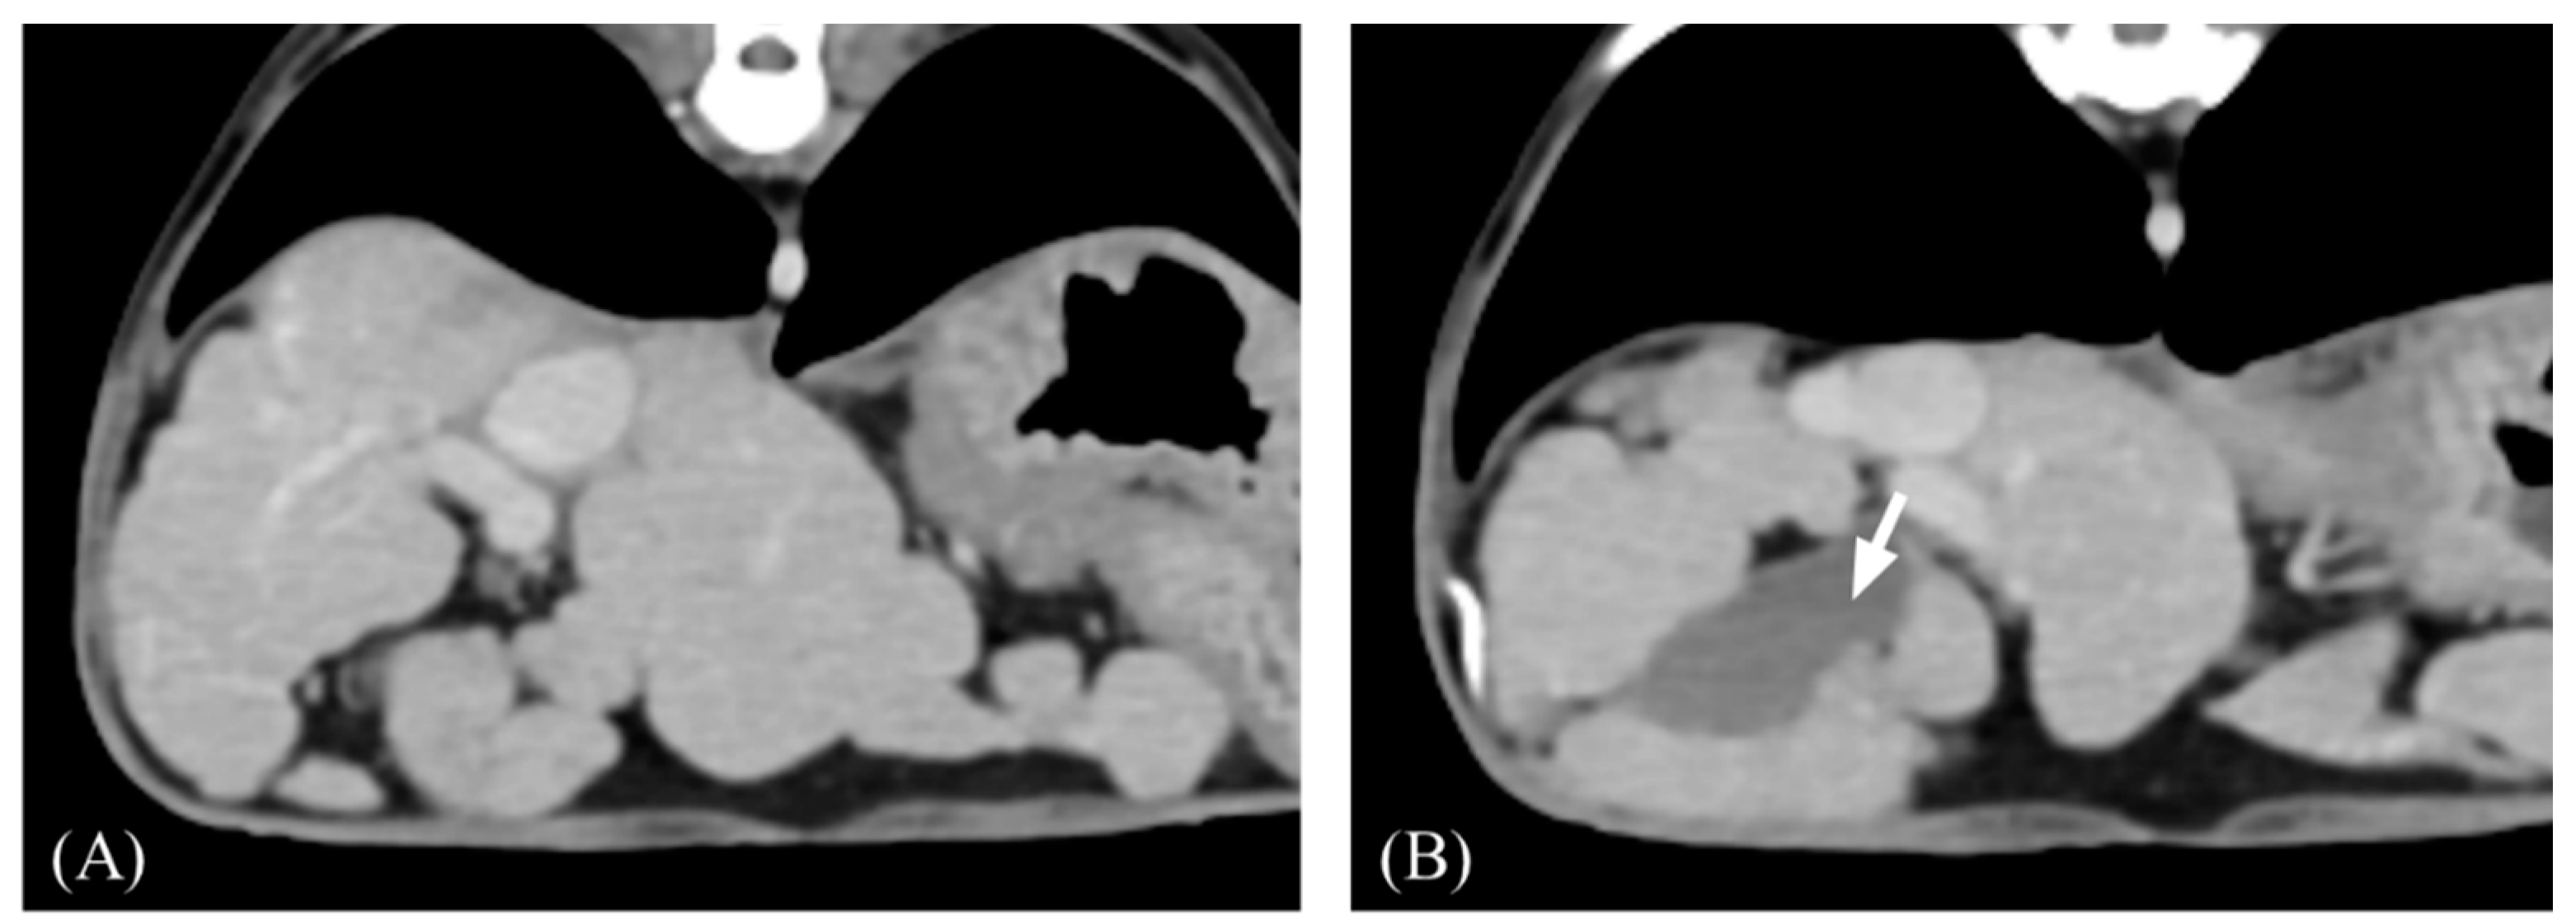

- Kim, T.; Baron, R.L.; Nalesnik, M.A. Infarcted Regenerative Nodules in Cirrhosis: CT and MR Imaging Findings with Pathologic Correlation. Am. J. Roentgenol. 2000, 175, 1121–1125. [Google Scholar] [CrossRef]

- Kim, Y.K.; Park, G.; Kim, C.S.; Han, Y.M. CT and MRI Findings of Cirrhosis-Related Benign Nodules with Ischaemia or Infarction after Variceal Bleeding. Clin. Radiol. 2010, 65, 801–808. [Google Scholar] [CrossRef]

- Scholtze, D.; Reineke, T.; Müllhaupt, B.; Gubler, C. Multiple Infarcted Regenerative Nodules in Liver Cirrhosis after Decompensation of Cirrhosis: A Case Series. J. Med. Case Rep. 2010, 4, 375. [Google Scholar] [CrossRef]